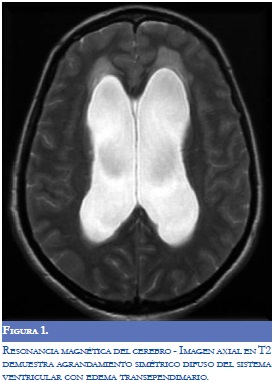

Los laboratorios realizados (hemograma, electrólitos, proteína C-reactiva, VDRL y VIH) fueron normales. Se realizó punción lumbar pero no se obtuvo retorno de líquido cefalorraquídeo (LCR) por bloqueo del espacio subaracnoideo. El LCR se obtuvo por medio de ventriculostomía externa y su análisis mostró hipoproteinorraquia; posteriormente se realizó derivación ventriculoperitoneal y se realizó un segundo análisis de LCR (Tabla 1). La reacción en cadena de polimerasa para tuberculosis fue negativa en LCR (otros análisis se encontraron normales). Los niveles de inmunoglobulina G en sangre fueron positivos para cisticerco (Índice IgG de 4,57; V.R. menor de 0,35). La primera resonancia magnética del cerebro realizada al ingreso al servicio de urgencias mostró marcada hidrocefalia (Figura 1). Después de la ventriculostomía externa, y la colocación de la derivación ventrículoperitoneal, la tomografía axial computarizada del cerebro (TAC) mostró múltiples nódulos calcificados sugestivos de NCC sin edema perilesional (Figura 2). La RM de la médula espinal reveló paquimeningitis generalizada, realce meníngeo y lesiones nodulares sugestivas de NC subaracnoidea (Figura 3). Otros estudios imaginológicos como TAC toracoabdominal con contraste y gamagrafía ósea se encontraron dentro de los límites normales. La biopsia meníngea realizada reveló la presencia de células fibrosas monomórficas rodeadas por tejido colagenosos, sin parásitos, compatible con inflamación crónica o hidrocefalia crónica.

El estadio final se desarrolla cuando los quistes evolucionan a la fase calcificada, donde se convierten en nódulos calcificados e inertes. Esta fase es la más frecuente y el diagnóstico se realiza principalmente mediante la TAC simple, que muestra múltiples lesiones pequeñas hiperdensas sin edema perilesional. Aunque en la RM estas lesiones inactivas pueden realzar con gadolinio, en esta etapa la TAC adquiere más importancia que la RM debido a su sensibilidad para identificar calcificaciones (Figuras 2 y 3).